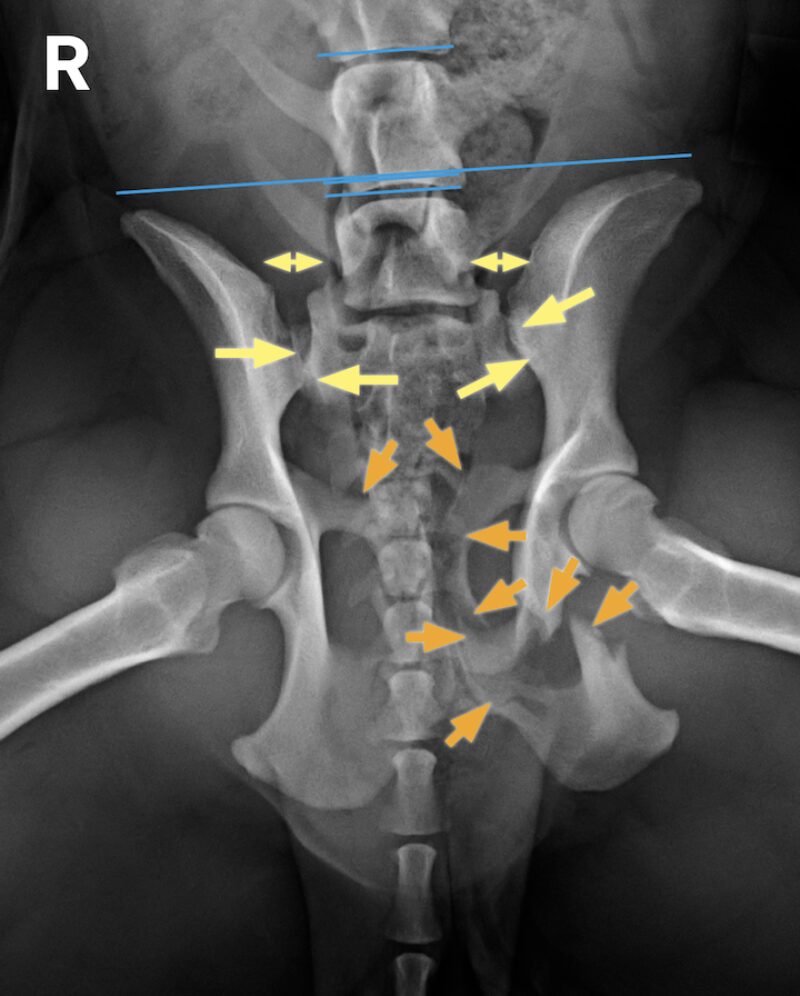

In Folge eines Autounfalls erlitt ein 2 Jahre alter Podenco (weiblich) ein Trauma und kann seitdem nicht mehr gehen. Auch stehfähig ist der Patient nur mit Unterstützung. Der klinische Befund ist links schlechter als rechts. Der Röntgenbefund zeigt eine Schambein- und Sitzbeinfraktur links mit Symphysenfraktur bzw. Symphysiolyse. Zu erkennen ist eine bilaterale iliosakrale Luxation mit langerungsbedingt variabler Darstellung. Die Aufnahmen geben damit Antwort auf die nach einem Unfall häufige Frage, ob das Iliosakralgelenk luxiert ist und eine Diastase vorliegt oder nicht. Eine normale anatomische Situation zeigt stufenlose Gelenkflächenkonturen von Darmbein (Ilium) und Sakrumflügel sowie einen schmalen Gelenkspalt.

Definition: Die Luxation eines straffen Gelenks wird auch Diastase (Auseinanderstehen) genannt. Beispiel: iliosakrale Diastase. Das Trauma trifft die Patienten meist kaudal am Becken und disloziert das Becken meist nach kranial.

• Leicht dislozierte Diastasen oder Sakrumfrakturen sind aufgrund von Überlagerungen beim Röntgen manchmal nicht zuverlässig zu sehen.

• Ein Vergleich der Parallelität einer Tangente entlang der Darmbeinflügel mit Tangenten entlang der Endplatten der kaudalen Lendenwirbel kann leichte Asymmetrien aufdecken helfen.